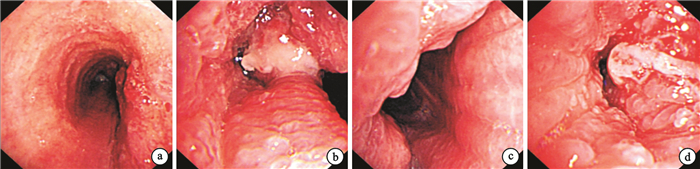

臨床資料????患者男性,67歲,因“咳嗽、咳痰及痰中帶血1個月”入院。患者1個月前無明顯誘因出現咳嗽、咳痰伴痰中帶血,感活動后胸悶、氣促。患者無發熱及胸痛。在外院肺部CT提示“氣管占位性病變,多考慮惡性腫瘤”,為確診于我院就診。患者發病以來一般情況可,體重未見減輕。既往有糖尿病病史10余年,個人史及家族史無特殊。查體可聞及吸氣相哮鳴音,余未見明顯異常。實驗室檢查:血常規、肝功能、腎功能、大便常規、小便常規正常。癌胚抗原(CEA)2.58 ng/mL,神經元特異性烯醇化酶(NSE)6.81 ng/mL,細胞角蛋白19片段(CYFRA21-1)2.55 ng/mL。血沉61 mm/1 h。心電圖、腹部彩色超聲未見異常。患者電子支氣管鏡檢查提示雙側主支氣管黏膜腫脹、粗糙,表面多發顆粒樣小結節(圖 1)。支氣管刷片示:部分上皮細胞增生,查見少量壞死物和極少量核異質細胞,非小細胞癌待排除。氣管下段取活組織病理檢查,結果示支氣管黏膜輕~中度慢性炎癥,部分支氣管上皮鱗化。支氣管鏡灌洗液中未查見惡性細胞。由于患者支氣管刷片查見極少量核異質細胞,3 d后再次在電子支氣管鏡下左主支氣管取活組織送病理檢查,結果示黏膜膜中~重度慢性炎癥,小血管周見淡軟無定性蛋白質,經剛果紅和堿性剛果紅染色均(-)。病理檢查結果2次均為慢性炎癥改變。患者出院并口服莫西沙星,囑門診隨訪支氣管病灶情況。出院后1個月患者再次因“痰中帶血”入院,且感活動后氣促較前加重。再次行電子支氣管鏡檢查,結果提示雙側主支氣管病變較前明顯加重(圖 2)。在氣管下段取活組織病理檢查,結果提示黏膜慢性炎,上皮廣泛鱗化,呈乳頭狀增生,上皮下方纖維組織增生,剛果紅染色未查見確切淀粉樣物質。活檢組織高危型人乳頭狀瘤病毒(HPV-HR)檢測(-)。痰及灌洗液中查3次均未見抗酸桿菌。病理科復核3次病理檢查,診斷氣管乳頭狀瘤。應用重組人干擾素α-2b 300萬U皮下注射10 d,患者感氣促較前明顯緩解,復查電子支氣管鏡提示,氣管內病灶較前明顯好轉(圖 3)。患者好轉出院。